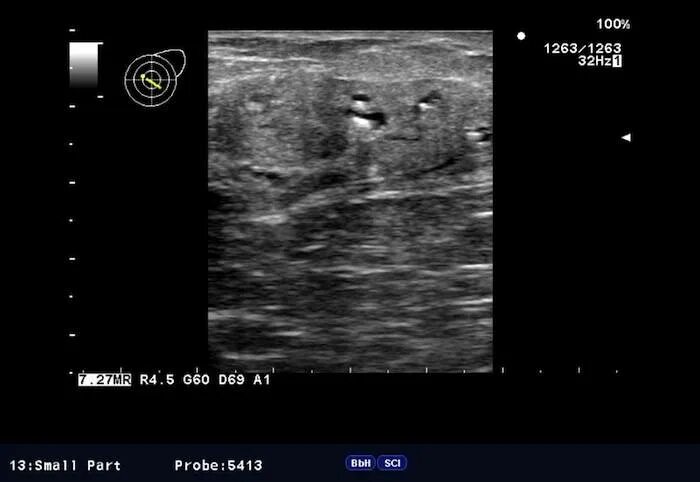

Кальцинат узи